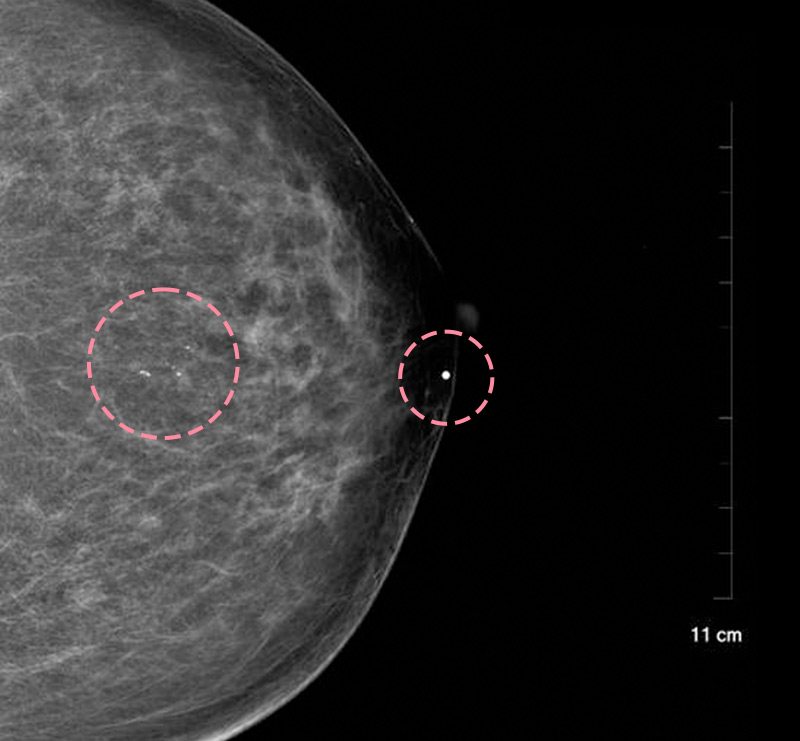

보형물 가슴성형 후 제법 크기가 있는 종양이 발견된 사례입니다.

가슴성형 후 맘모톰시술은 보형물의 위치를 파악하면서 바늘을 다루어야 하기 때문에 고도의 숙련도와 정밀한 판독 능력이 필요합니다.

한송이 원장은 다양한 사례를 접해온 경험과 전문성을 바탕으로 시술을 성공적으로 마쳤습니다.

총조직검사 후 최종 진단 결과 양성 종양(섬유선종)으로 확인되어 맘모톰 시술로 제거를 진행했습니다. 7개월 경과 후 검사를 통해 인공 보형물의 누수 및 파손 없이 깨끗한 내부 상태가 확인되었습니다.